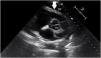

La infección por COVID-19 altera principalmente la función pulmonar, aunque también se han reconocido manifestaciones extrapulmonares. Hasta el momento se sabe que una de las complicaciones cardiovasculares más comunes asociadas al COVID-19 es la pericarditis, que puede presentarse en su severidad extrema con taponamiento cardiaco, el cual puede tener un desenlace fatal si no es reconocido y tratado a tiempo. En el actual reporte de caso describimos el caso anecdótico de una paciente de 39 años, sin antecedentes patológicos de importancia, quien previamente ha recibido 2 dosis de ARNm-1273 para SARS-CoV-2 con la última dosis aplicada al menos 3 meses después de un cuadro clínico compatible con taponamiento cardiaco secundario a pericarditis por SARS-CoV-2; su evolución fue satisfactoria tras drenaje por videotoracoscopia del líquido pericárdico, así como uso de colchicina.

COVID-19 infection mainly alters lung function, although extrapulmonary manifestations have also been recognized. Up to now, it is known that one of the most common cardiovascular complications associated with COVID-19 is pericarditis, which can present at its extreme severity with cardiac tamponade, which can have a fatal outcome if it is not recognized and treated in time. In the current case report, we describe the anecdotal case of a 39-year-old patient, with no significant pathological history, who has previously received 2 doses of mRNA-1273 for SARS-CoV-2 with the last dose applied at least 3 months after a clinical picture compatible with cardiac tamponade secondary to pericarditis due to SARS-CoV-2, its evolution was satisfactory after drainage by video-assisted thoracoscopy, as well as use of colchicine.